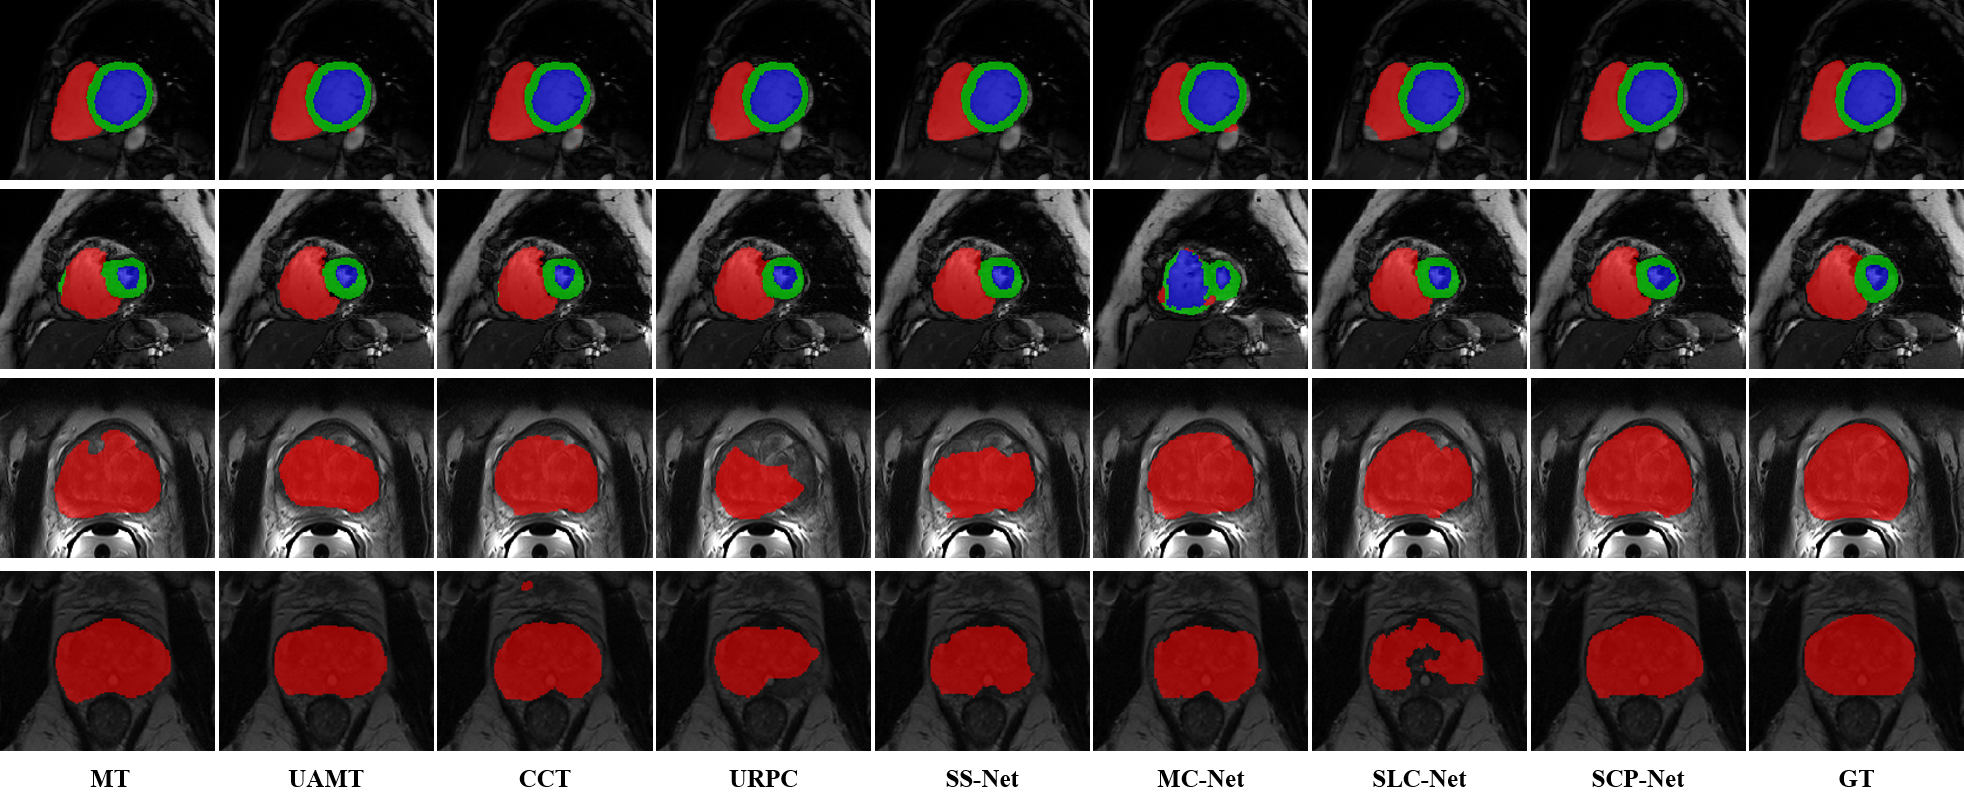

Refer to caption

Figure 2: Visualized segmentation results of different methods on ACDC and PROMISE12. SCP-Net better preserves anatomical morphology compared to others.

Comparision with Other Methods. To demonstrate the effectiveness of SCPNet, we compare it with 7 state-of-the-art methods for semi-supervised segmentation and fully-supervised (100% labeled ratio) limited supervised (10% labeled ratio) baseline. The quantitative analysis results of ACDC dataset are shown in Table 1. SCP-Net significantly outperforms the limited supervised baseline by 7.02%, 6.13%, and 6.32% on DSC for RV, Myo, and LV, respectively. SCP-Net achieves comparable DSC and ASSD to the fully supervised baseline. (89.69% vs 91.78 and 0.73 vs 0.52). Compared with other methods, SCP-Net achieves the best DSC and ASSD, which is 1.58% and 0.24 higher than the second-best metric, respectively. Moreover, we visualize several segmentation examples of ACDC dataset in Fig. 2. SCP-Net yields consistent and accurate segmentation results for the RV, Myo, and LV classes according to ground truth (GT), proving that the unsupervised prototypical consistency constraints effectively extract valuable unlabeled information for segmentation performance improvement. Table 3 in supplementary material reports the quantitative result for prostate segmentation. We also perform the limited supervised and fully supervised training with 10% labeled ratio and 100% labeled ratio, respectively. SCP-Net surpasses the limited supervised baseline by 16.18% on DSC, and 10.35 on ASSD. In addition, SCP-Net gains the highest DSC of 77.06%, which is 5.63% higher than the second-best CCT. All improvements suggest that SPCC and CPCC are beneficial for exploiting unlabeled information. We also visualize some prostate segmentation examples in the last two rows of Fig. 2. We can observe that SCP-Net generates anatomically-plausible results for prostate segmentation.